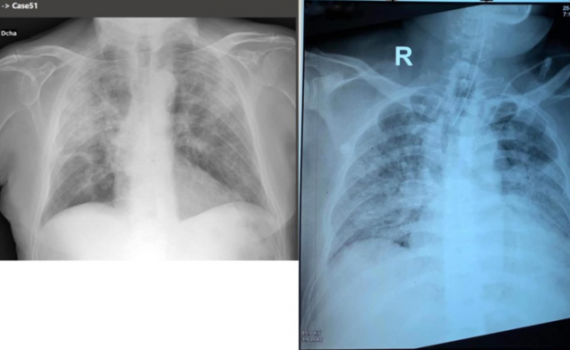

Dùng AI chẩn đoán tình trạng bệnh nhân Covid-19

Công nghệ AI giúp bác sĩ nhận biết tỷ lệ nhiễm virus trên phổi của bệnh nhân để sàng lọc, tập trung xử lý các ca nặng, nguy kịch.

AI chẩn đoán người nhiễm nCoV trong 20 giây

Bệnh viện Xiaotangshan ở Hà Nam (Trung Quốc) ứng dụng công nghệ AI để đọc phim chụp cắt lớp giúp xác định bệnh nhân Covid-19 với độ chính xác 96%.